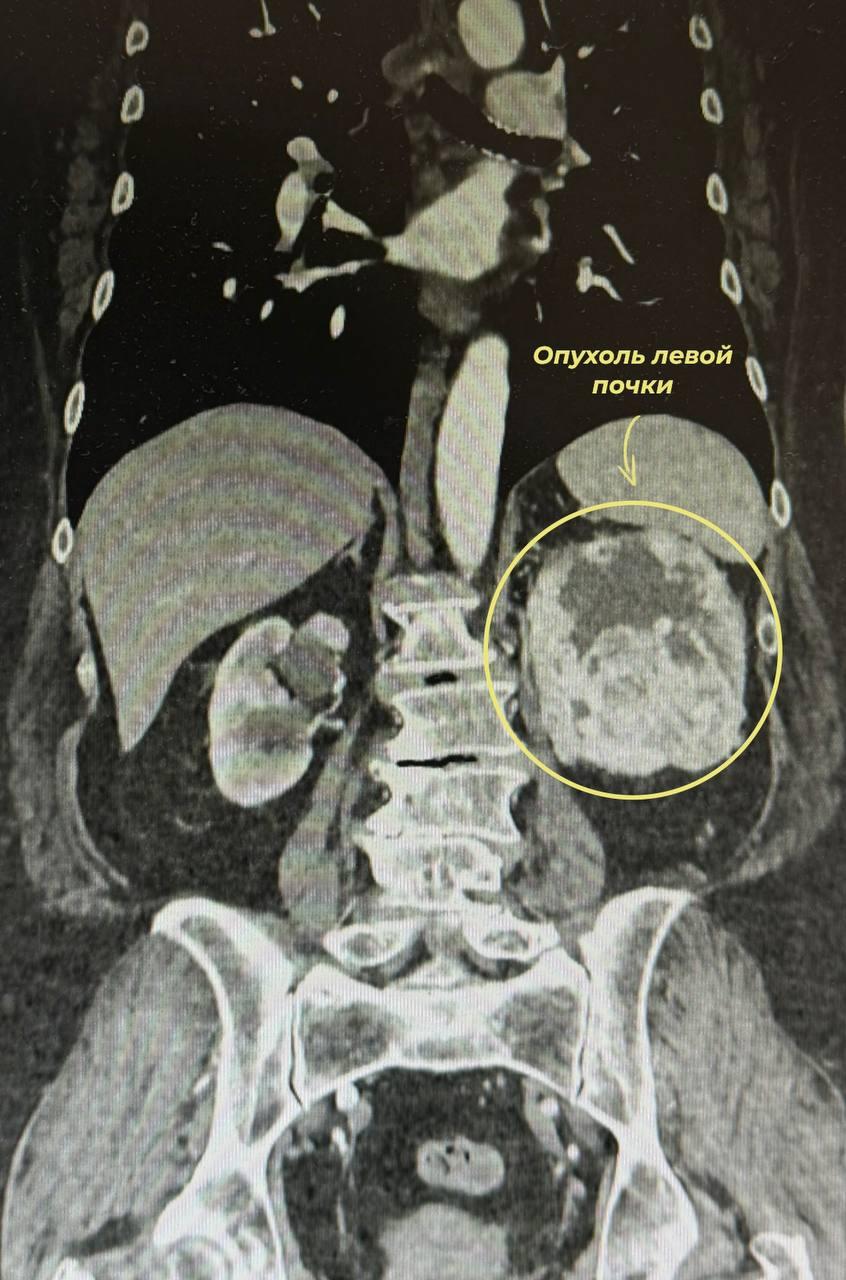

В Ивановский областной онкодиспансер обратилась пациентка с жалобами на тянущие боли в поясничной области слева и эпизоды гематурии (крови в моче). Ранее она была направлена на амбулаторное наблюдение онкологом. При дообследовании — МСКТ трёх полостей с контрастированием (диск пересмотрен в онкодиспансере) — выявлено злокачественное новообразование левой почки, оцененное по системе R.E.N.A.L. в 10 баллов.

Система R.E.N.A.L. (оценка размера, экзофитного роста, близости к собирательной системе и сосудам) позволяет объективизировать тактику. 10 баллов — это опухоль максимальной анатомической сложности, требующая высокой квалификации хирурга.